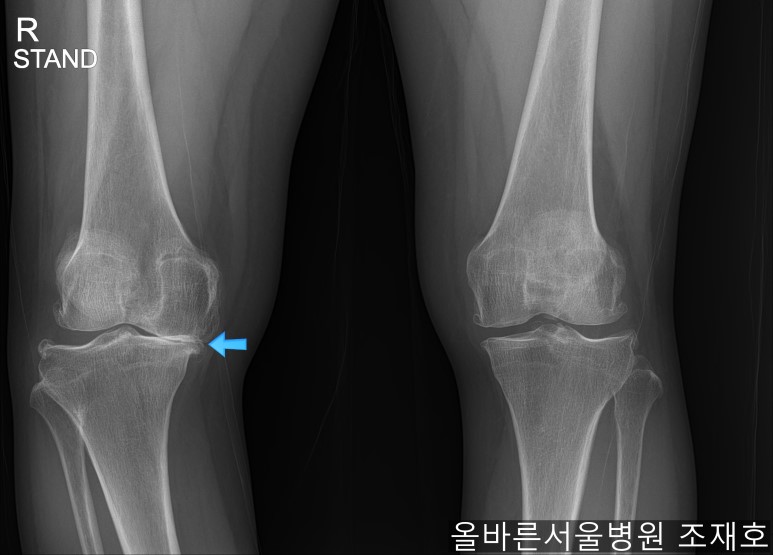

某患者,女,54岁,大面积软骨损伤,伴随内翻畸形,实施非切开CARTSTIEM手术及胫骨近端外翻截骨术,2、3年前右侧膝盖开始疼痛,在其他医院做了两次关节镜手术后疼痛加剧,膝关节变形严重遂到本院接受治疗。

仅通过放射线片子观察到:右膝由于炎症严重,内侧胫骨及股骨已接触在一起,向内测严重变形。

膝虽然也观察到了炎症,但远不如右膝严重。

如果通过X光片也观察到相同的病症,可以判断内侧关节的软骨大部分都损伤了。